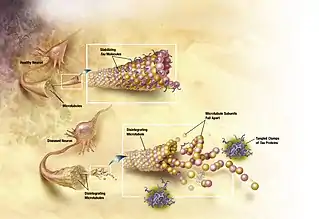

The tau hypothesis proposes that tau protein abnormalities initiate the disease cascade.[49] In this model, hyperphosphorylated tau begins to pair with other threads of tau as paired helical filaments. Eventually, they form neurofibrillary tangles inside nerve cell bodies.[68] When this occurs, the microtubules disintegrate, destroying the structure of the cell's cytoskeleton which collapses the neuron's transport system.[69]

Alzheimer's disease is also considered a tauopathy due to abnormal aggregation of the tau protein. Every neuron has a cytoskeleton, an internal support structure partly made up of structures called microtubules. These microtubules act like tracks, guiding nutrients and molecules from the body of the cell to the ends of the axon and back. A protein called tau stabilises the microtubules when phosphorylated, and is therefore called a microtubule-associated protein. In Alzheimer's disease, tau undergoes chemical changes, becoming hyperphosphorylated; it then begins to pair with other threads, creating neurofibrillary tangles and disintegrating the neuron's transport system.[98] Pathogenic tau can also cause neuronal death through transposable element dysregulation.[99] Necroptosis has also been reported as a mechanism of cell death in brain cells affected with tau tangles.[100][101]